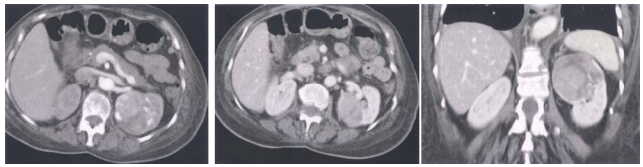

73 55 歲林先生,近數月來感覺疲倦、食慾減退,右上腹部也感到有些脹痛。血液檢查胎兒蛋白(alphafetoprotein)值正常、HBsAg 陽性(HBsAg +),肝臟 Dynamic CT 影像如圖⑴,手術前再度做血管 攝影檢查如圖⑵。林先生最可能患了什麼病? 圖⑴ 圖⑵ (A)肝臟轉移腫瘤(liver metastasis) (B)膽管癌(cholangiocarcinoma) (C)肝細胞癌(hepatocellular carcinoma) (D)海綿狀血管瘤(cavernous hemangioma)